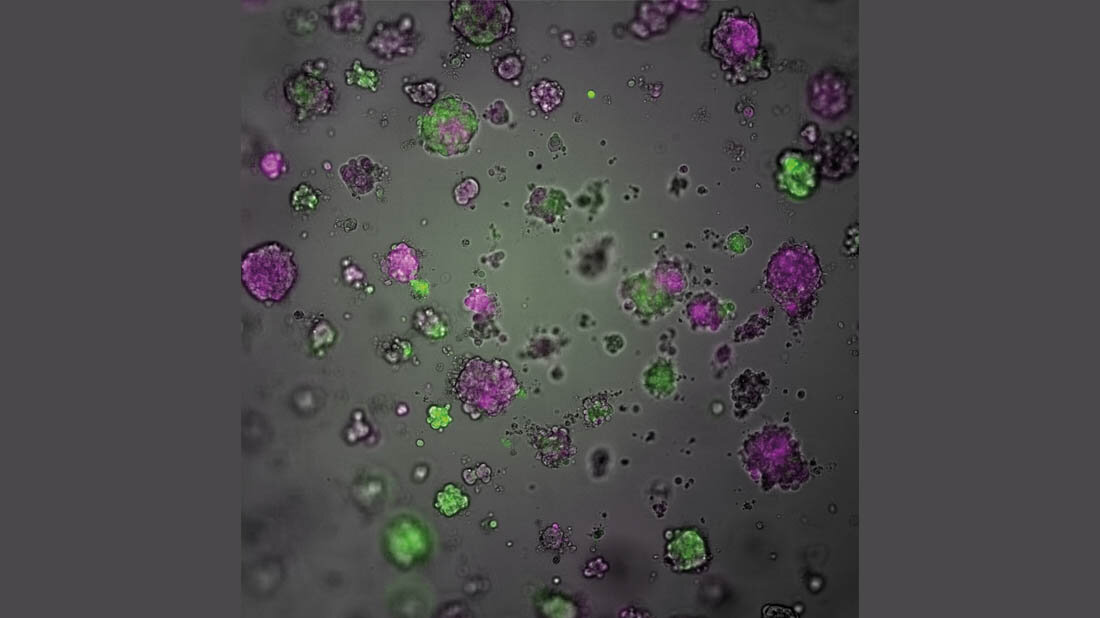

Weitere Versuche der Forscherinnen und Forscher bestätigten, dass der Verlust von NF1 auch in menschlichen Krebszellen und aus Tumoren gezüchtetem Gewebe zur Resistenz führt. „Das Fehlen von NF1 ist also der Elefant im Raum, der in der Zelle alles durcheinanderbringt und den Therapieerfolg verhindert“, so Bentires-Alj. Eine Analyse zeigte, dass der Verlust von NF1 Auswirkungen auf den Energiehaushalt der Zelle hat: „Sie produzieren nicht mehr so viel Energie mit Hilfe von Mitochondrien, sondern weichen auf andere Wege der Energieproduktion aus“, sagt die Erstautorin der Studie, Dr. Priska Auf der Maur.